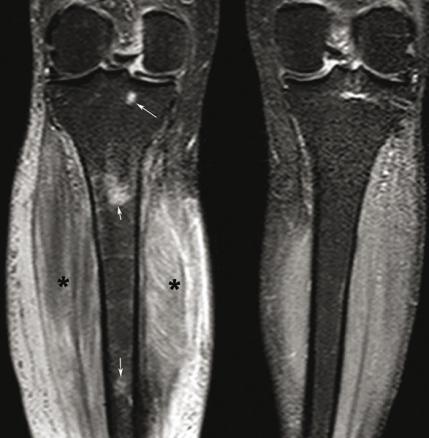

© Sylvain Poirée - La Revue du Praticien Imagerie par résonance magnétique, coupe coronale centrée sur les jambes en pondération T2, STIR montrant des hypersignaux de l'os médullaire du tibia droit (flèches) et des parties molles (*).